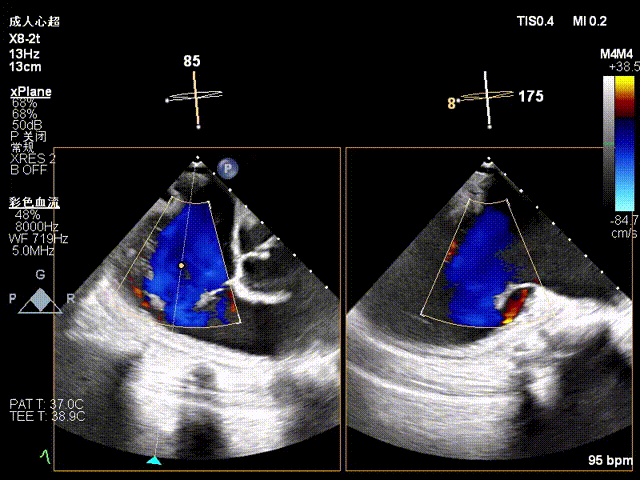

Baseline regurgitation after anesthesia

Postoperative regurgitation